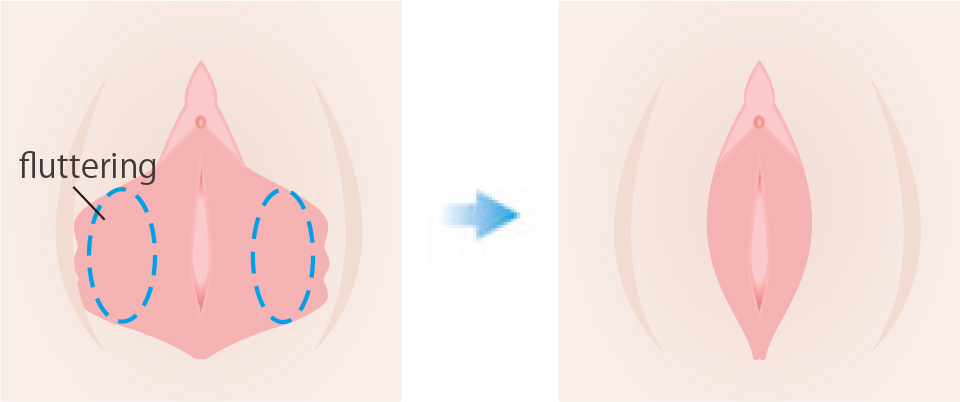

This surgery is performed to improve the size of the labia minora and the difference between the left and right sides. If there is too much protrusion or a left-right discrepancy, the excess labia minora are removed and beautifully reshaped by sewing them back together.

Recommended for people with these problems